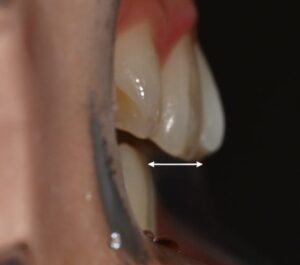

성인 이소맹출, 어금니 반대교합 총생(덧니)가 있을 때 치아 교정

안녕하세요, 교정과 전문의 김정은입니다. ​ 모든 영구치가 알맞은 자리에 나오면 좋겠지만, 그렇지 못하고 제 위치가 아닌 자리에 자라날 때도 있는데요. ​ 이처럼 구강 속 정상적으로 나와야 될 영구치가 제 위치가…